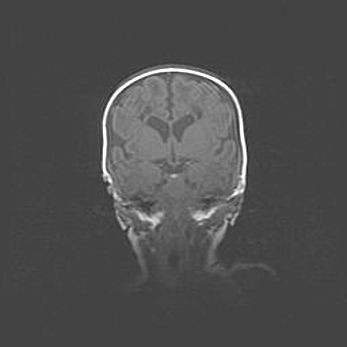

Множественные кисты обоих полушарий головного мозга, наибольшая из них в правой затылочной области. Ассиметричная атрофическая гидроцефалия.

Возраст: 7 месяцев

Вес: 5660 г

Пол: мужской

Окружность головы: 41,5 см

Срок гестации: 28-29 недель

Кисты головного мозга развиваются в результате многоочаговых некрозов вещества мозга и возникают вследствие перенесенной перинатальной инфекции, менингитов, энцефалитов, асфиксии, родовой травмы, расстройств мозгового кровообращения различного генеза. Образованию кист в веществе головного мозга плодов и новорожденных способствуют такие факторы, как высокое содержание в нем воды, недостаточная (или отсутствие) миелинизация и слабая астроглиальная реакция на повреждение.

Кисты могут сочетаться с гидроцефалией и другими поражениями головного мозга.